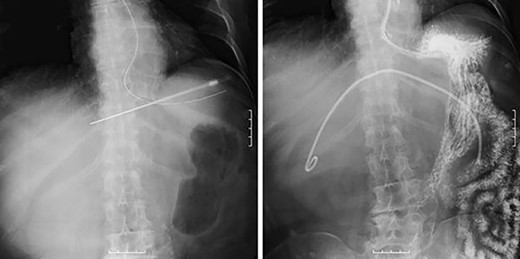

However, during hospitalization, the patient developed dehydration, acute renal failure, electrolyte imbalance and impaired consciousness. C-reactive protein level was elevated (9.61 mg/dL), indicating intracystic infection. As emergency treatment, percutaneous puncture drainage of the cyst was performed to decompress the stomach and duodenum (Fig. 4).

Percutaneous puncture drainage improved the obstruction of duodenum.

A total of 1400 mL of purulent fluid was drained, and cytology of the drainage fluid showed no malignant findings. The gastrointestinal obstruction symptoms improved, enabling oral food intake; thus, we decided to perform laparoscopic deroofing of the hepatic cyst.